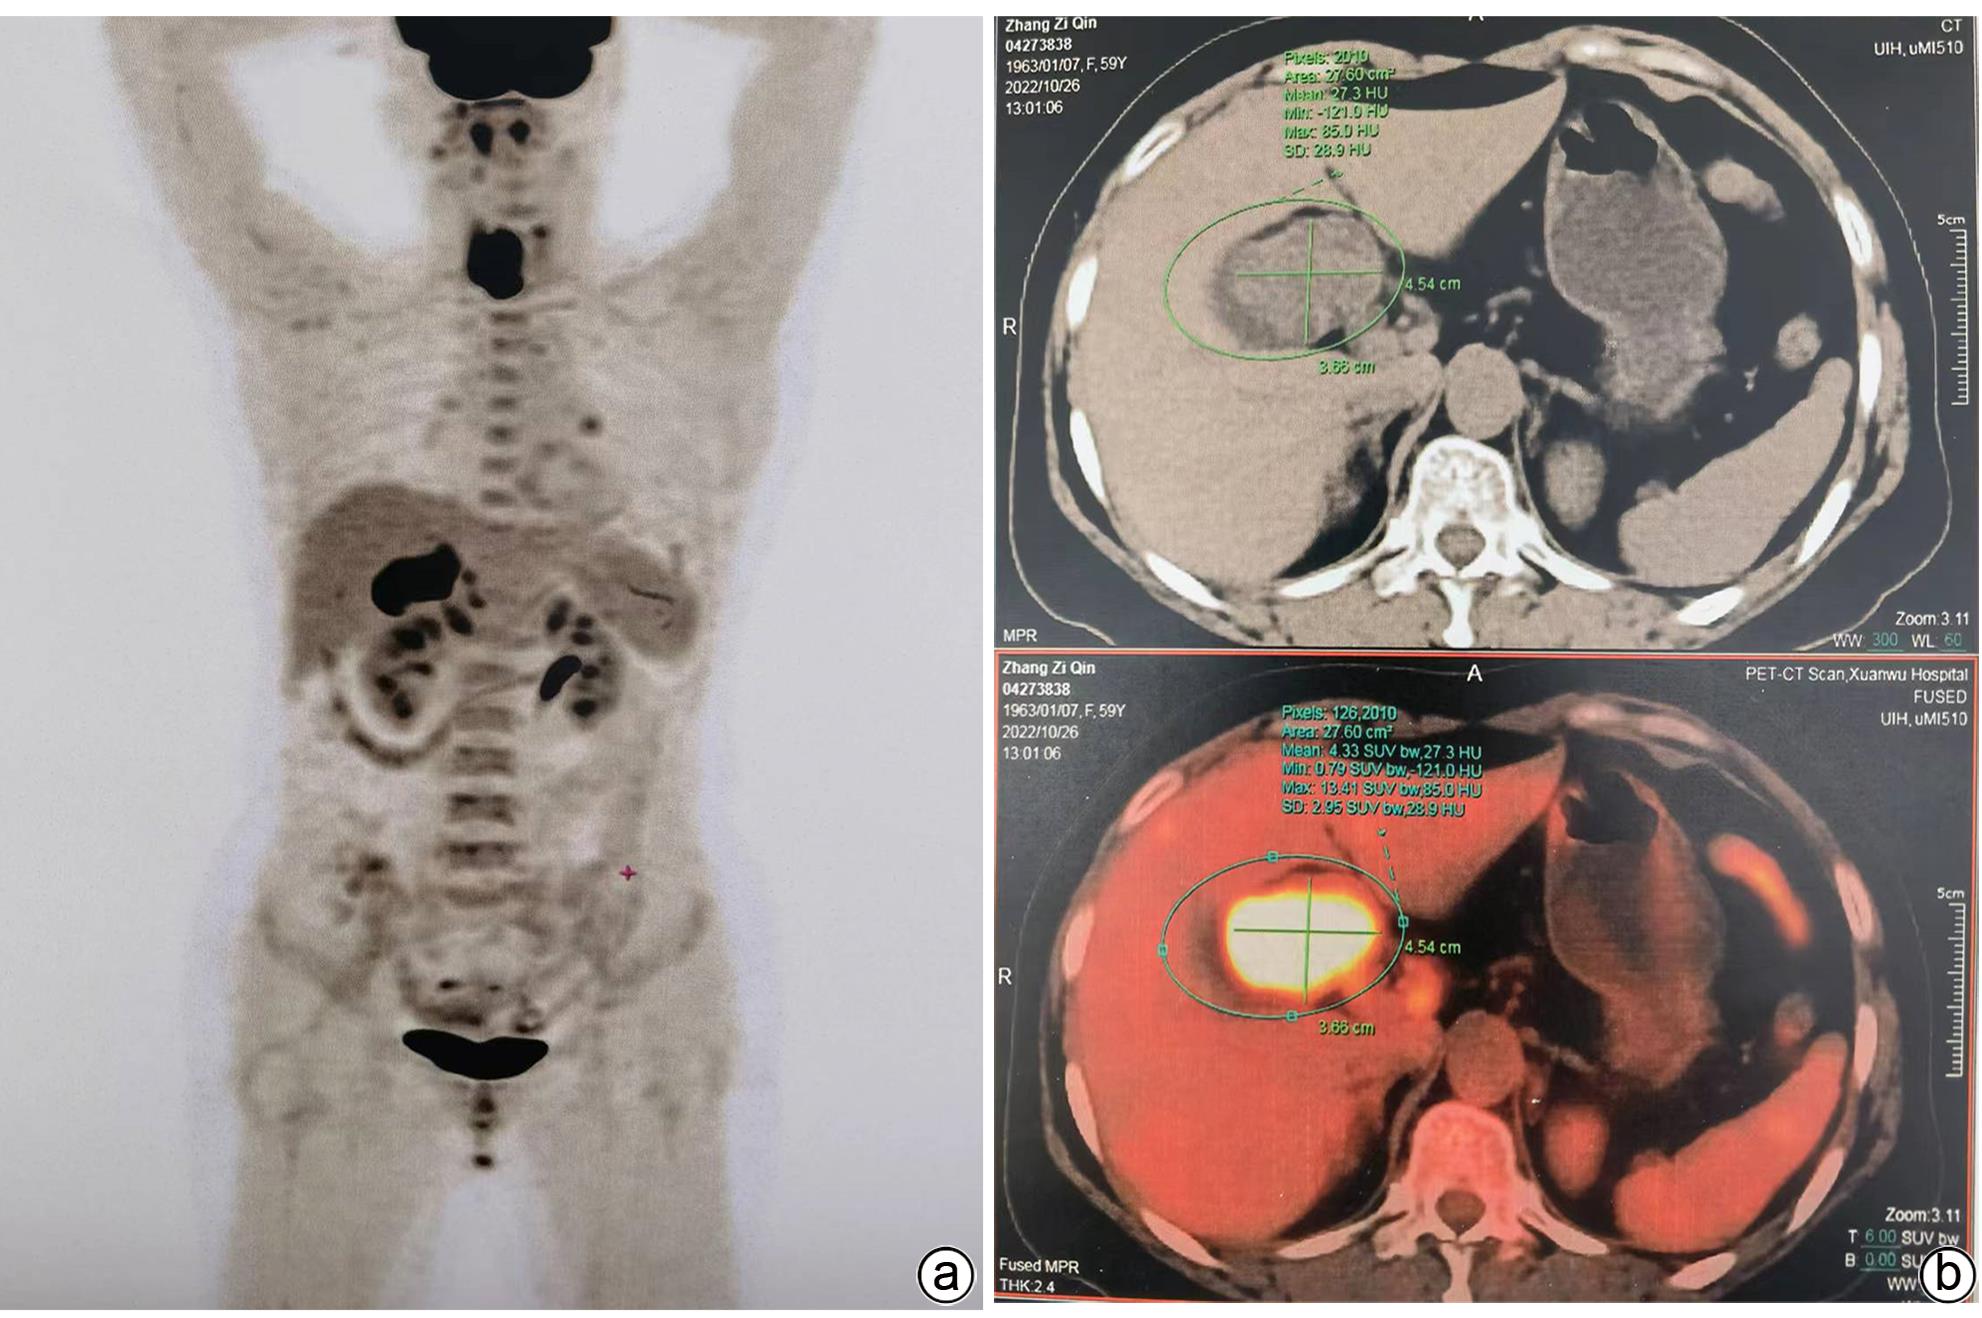

Giant adenoma of the gallbladder misdiagnosed as gallbladder carcinoma: A case report

Yuehua WANG, Hua JIANG, Lianghong TENG, Huanli DUAN, Bixiao CUI, Dongmei WANG

2024, 40(4): 794-796. DOI: 10.12449/JCH240424

Abstract(1183) HTML (564) PDF (1133KB)(65)

Abstract:

One patient with gallbladder mass had transient jaundice and was diagnosed with gallbladder carcinoma by abdominal ultrasonography, contrast-enhanced CT, MRCP, and PET-CT. Surgical exploration showed enlarged gallbladder and a mass in the neck of the gallbladder pressing against the hilum of the liver, with no manifestation of tumor invasion, and there were no signs of liver metastasis. Only cholecystectomy was performed for the patient. The pathological diagnosis was tubular adenoma of the gallbladder without carcinogenesis. This case is characterized by a large gallbladder tumor, without marginal infiltration on imaging or malignant transformation based on pathology.